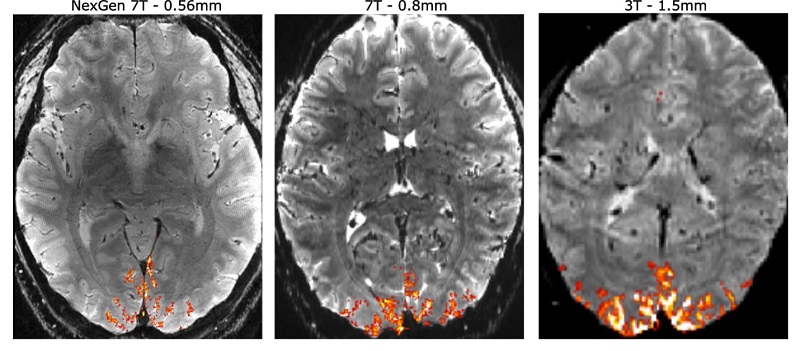

使用更高分辨率的下一代7T MRI(左)与传统7T扫描仪(中)和标准3T医院扫描仪(右)进行的人脑扫描的比较。凭借更高的分辨率,神经科学家可更精确地定位大脑中的信号(橙色),以了解正常的大脑回路以及与大脑疾病相关的变化。

图片来源:加州大学伯克利分校/先进MRI技术公司